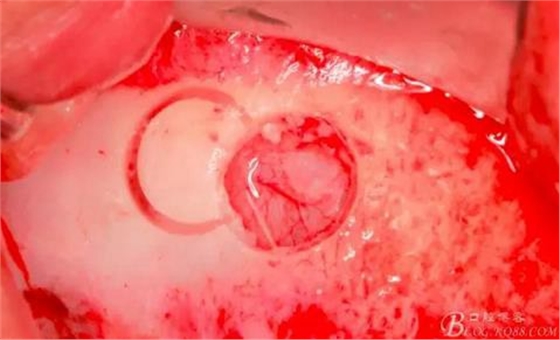

使用窗口擴大鉆,這也是這套工具盒里一個亮點,其前端是圓形高度光滑的,鉆體是有側(cè)切功能的。工作時用光滑的圓頭頂開已經(jīng)剝離的竇膜,用鉆體部分將窗口周邊不規(guī)則的部分磨掉,同時可以擴大窗口。